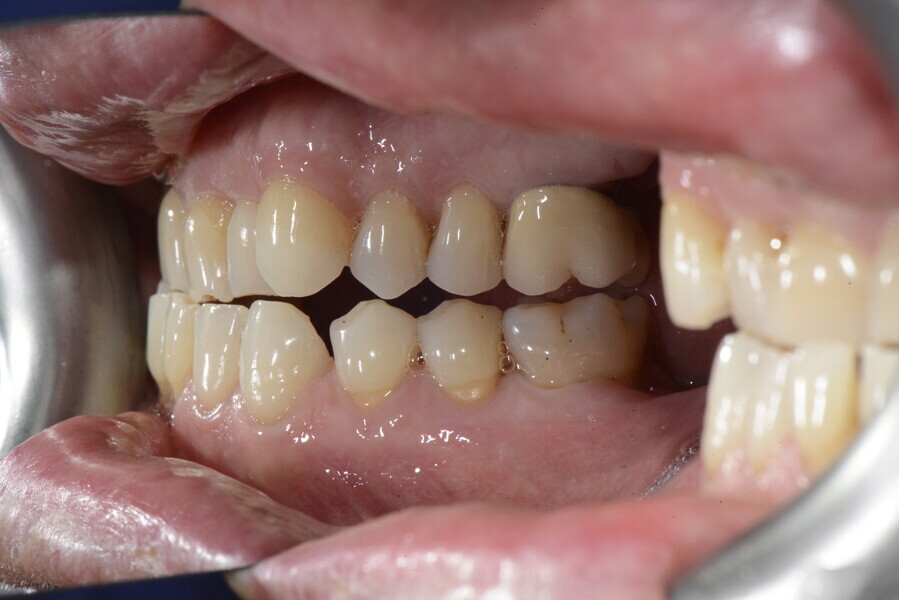

After the first phase of aligner treatment, we had achieved better inter-arch coherence, better maxillary arch expansion, and some space for improving the anterior tooth proportions restoratively (Fig. 19). We then temporarily restored the anterior teeth directly with composite, closing the spaces, improving the tooth proportions and further increasing the maxillary arch expansion (Fig. 20). We used restorative arch expansion to reduce the orthodontic destabilisation of the teeth to achieve the correct inter-arch coherence and retain the teeth in the cortical bone.38 A refinement aligner phase was undertaken to improve the final alignment of the gingival zenith and to improve the inter-arch coherence (Fig. 21). The periods of the first orthodontic phase and of the refinement were used to augment the mandibular and maxillary bone and to place the implants (Fig. 22). At the end of the orthodontic treatment, the case was finalised with ceramic veneers in the anterior area and temporary restorations on the implants in the posterior area (Figs. 23–26).

The provisional phase of about four months was important to allow the peri-implant tissue to mature and to teach the patient to chew correctly with chewing gum, cotton rolls and silicone masticatory sticks. This is fundamental training for the patient to achieve the correct alternating unilateral masticatory cycle needed to obtain the ideal rehabilitation of the masticatory system. We wanted the patient to achieve ideal masticatory and swallowing function. After sufficient rehabilitation time, we finalised the case with posterior zirconia crowns screwed on to the implants (Fig. 27).26

For maintenance purposes, after prosthetic finalisation, the patient was to carry on with the Froggymouth therapy and to use the Ri.P.A.Ra. for physiotherapeutic exercises and mastication training (Fig. 28). It was strongly recommended that the patient wear a mandibular occlusal splint during sleep. This occlusal splint was designed with disclusion guides to advance the mandible and ensure balanced contralateral support (Fig. 29).11, 39 We achieved an aesthetic appearance with adequate inter-arch coherence and a better cephalometric result (Figs. 30 & 31).